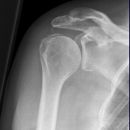

Schulter seitlich (Y-View)

Patient steht mit dem Bauch am Stativ (p.a.), gesunde Seite um 45° anheben, kranke Seite liegt auf, Arm der aufzunehmenden Seite im Ellenbogen um 90° gebeugt.

Senkrecht in Gelenkspalt bei Format 18/24.

Bei Format 24/30 oberer Kassettenrand: 2 Querfinger oberhalb der Schulter, prox. Humerus mit in der Einblendung.

Scapula stellt sich Y-förmig ohne Rippenüberlagerung dar. Humerus und Scapula überdecken sich. Gelenkpfanne befindet sich im Schnittpunkt der 3 Schenkel vom Y.